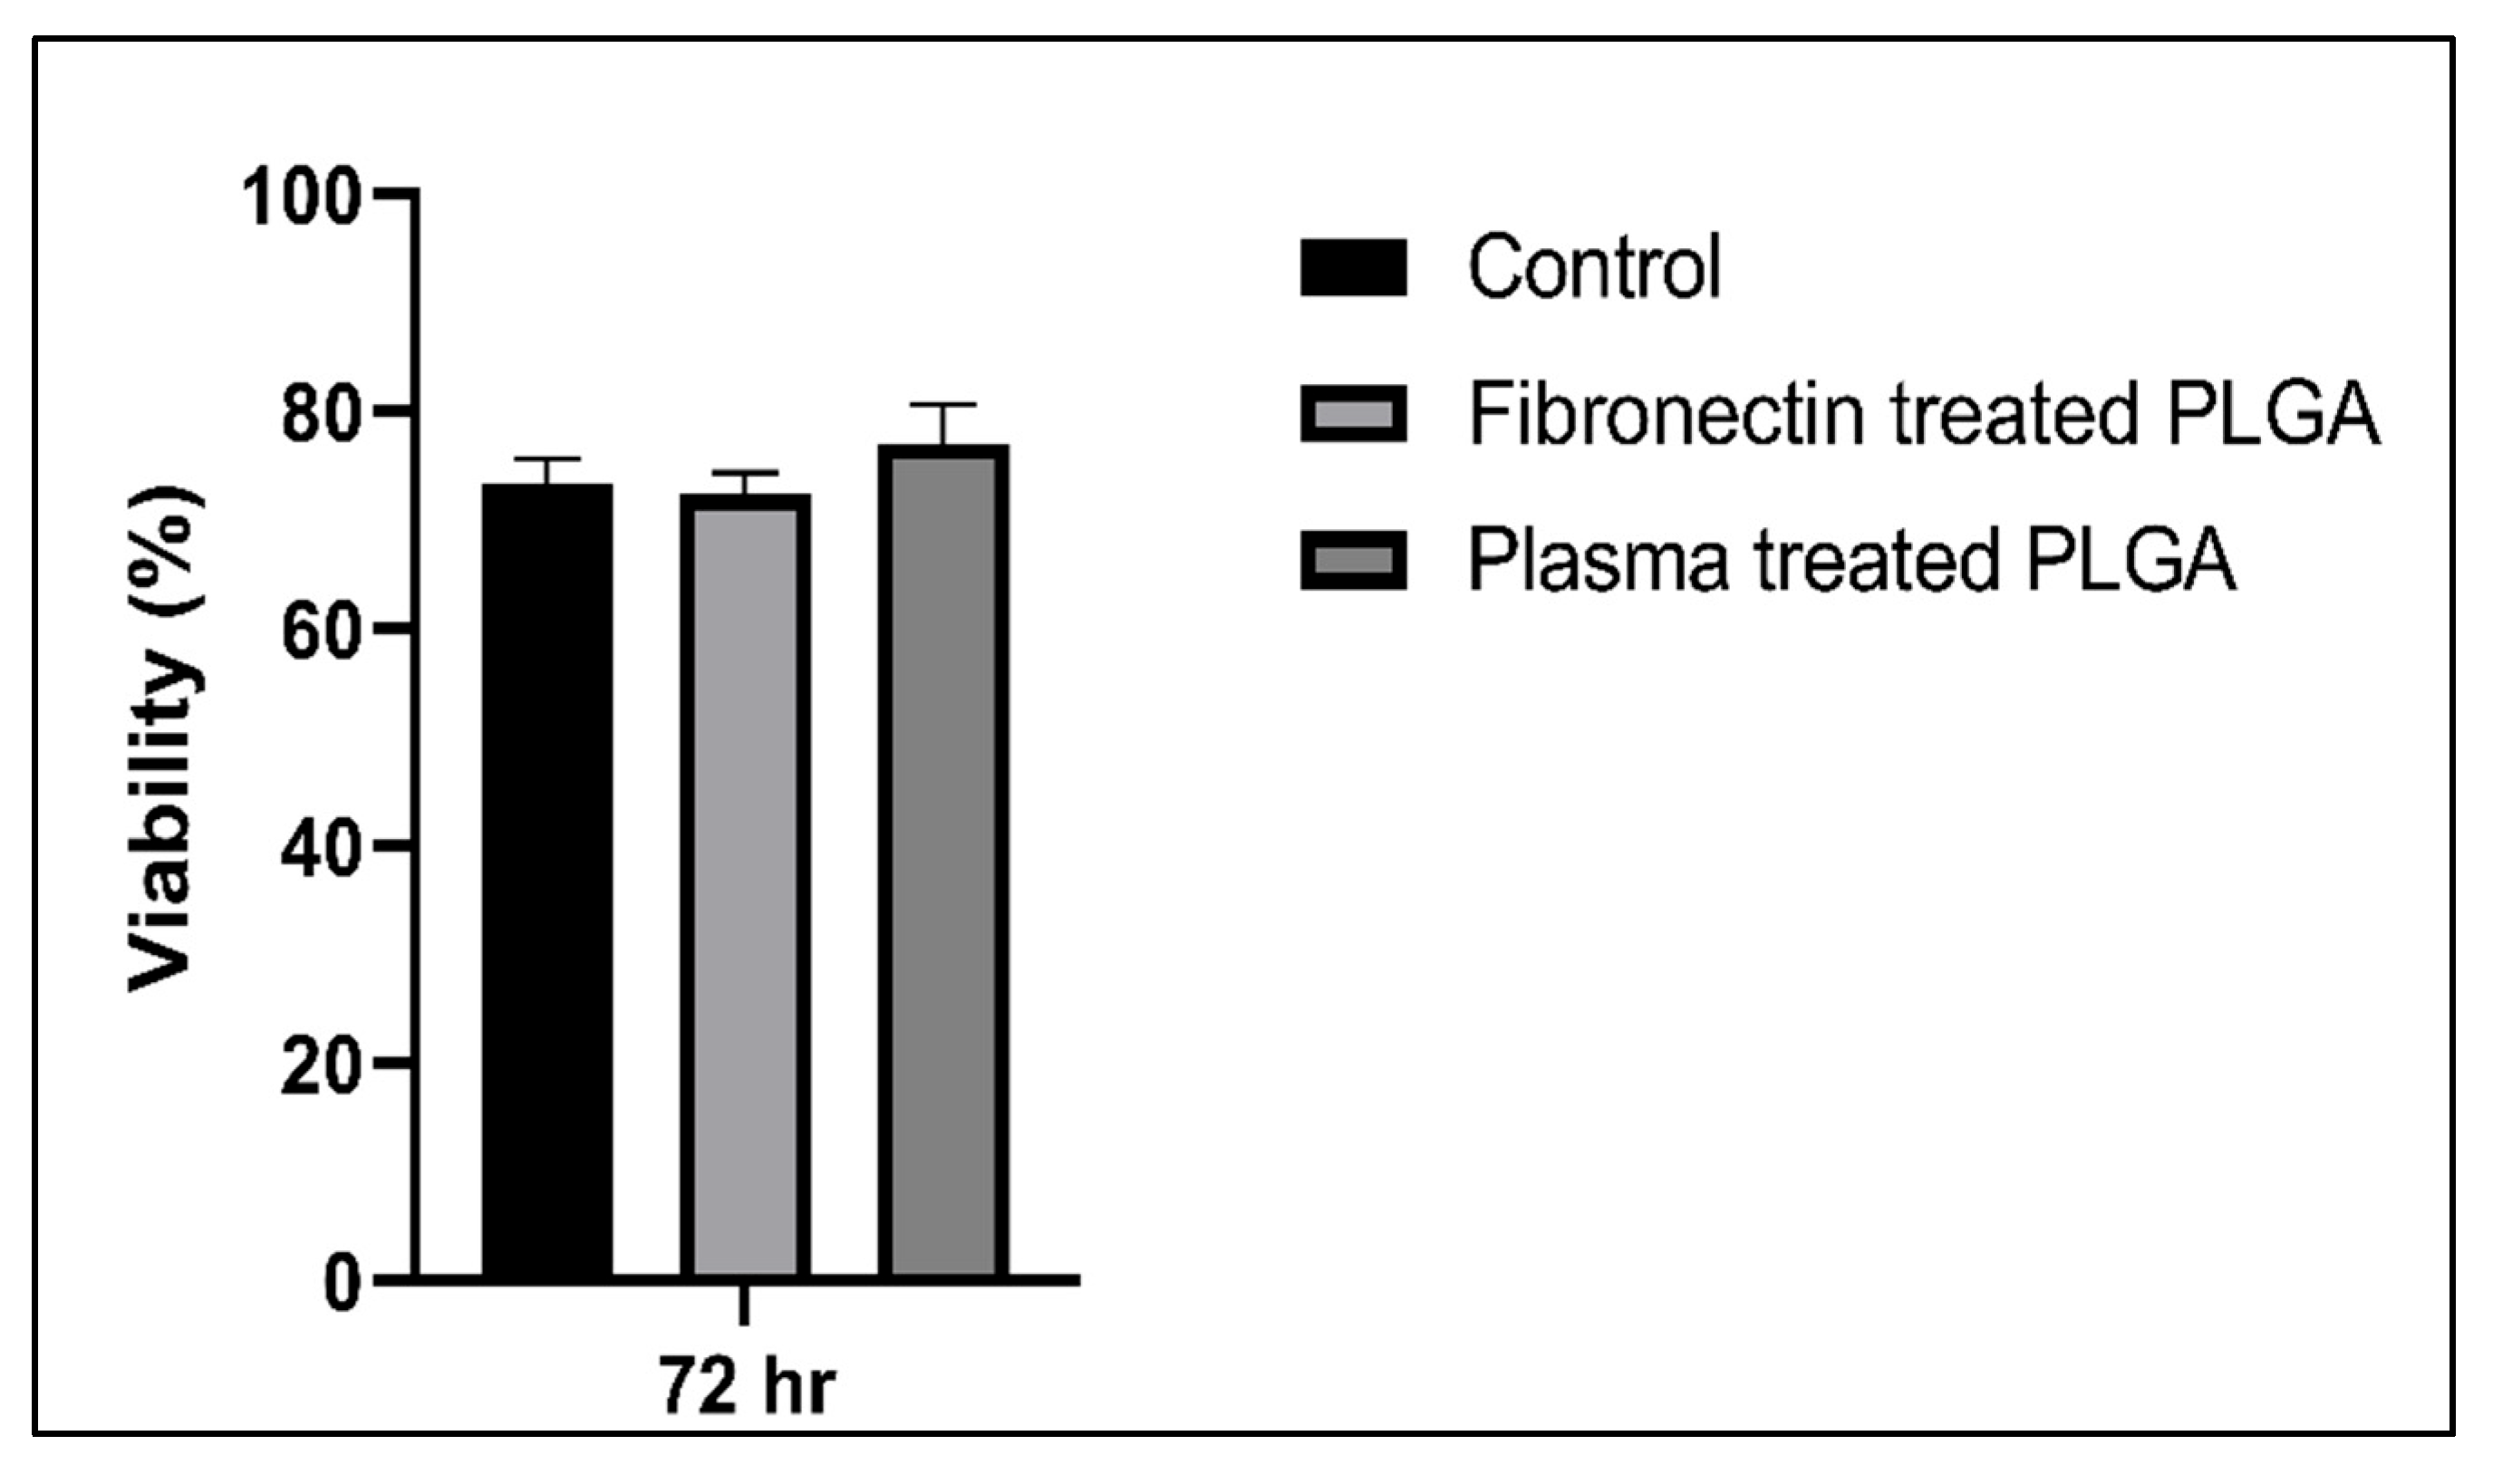

3.4.2. Cytotoxic Assay